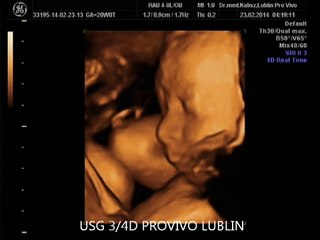

Echographie Souvenir 3D 4D chez Baby Live Montpellier